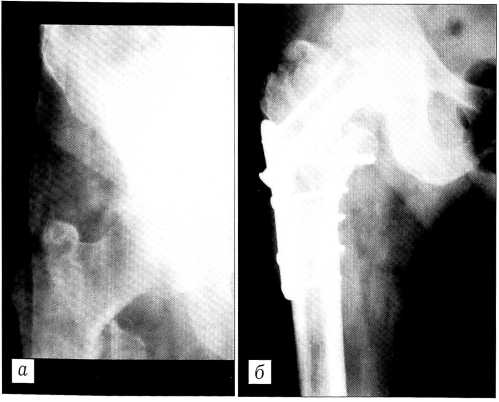

Больная Л.,68 лет, поступила в травматологическое отделение Самарской городской больницы № 1 им. Н.И. Пирогова 01.03.99 через 4 ч после травмы (падение на улице). Диагноз: закрытый чрезвертельный перелом правой бедренной кости со смещением отломков 31 А1.2. Сопутствующий диагноз: ишемическая болезнь сердца; атеросклеротический кардиосклероз Н1; гипертоническая болезнь III стадии. При поступлении выполнены новокаиновая блокада места перелома и иммобилизация в гипсовом деротационном сапожке. Предоперационное обследование и подготовка проведены с участием терапевта и анестезиолога.

03.03.99 произведен остеосинтез вертельной области правого бедра новым устройством. Продолжительность операции — 38 мин, кровопотеря — 150 мл. Послеоперационный период протекал без осложнений. Больная выписана через 15 сут после травмы. Через 3 мес самостоятельно ходила по улице, пользуясь тростью. При осмотре через 4 мес после операции: полное восстановление функции оперированной конечности, пациентка обслуживает себя, выполняет работу по дому и на огороде (рис. 4).

Рис. 4. Рентгенограммы правого тазобедренного сустава больной Л. 68 лет. а — при поступлении: чрезвертельный перелом правой бедренной кости со смещением отломков, тип 31 А1.2; б — после остеосинтеза; в — через 3 мес: перелом сросся.